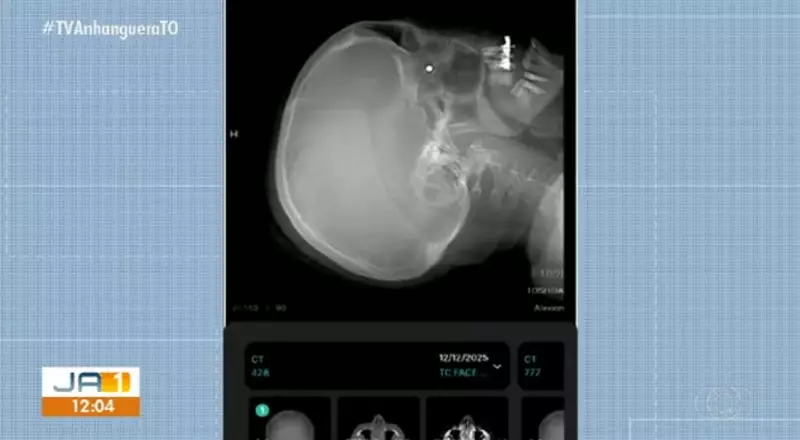

Exames de raio-X confirmaram a gravidade da situação: o chumbinho está alojado atrás do globo ocular de Isabel. Até o momento, a servidora já passou por quatro oftalmologistas, e a orientação unânime tem sido a de não retirar o projétil.